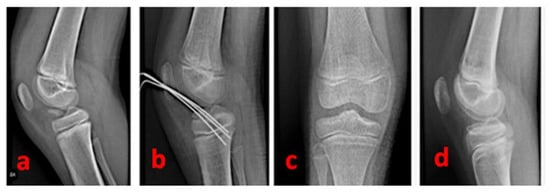

A complete clinical recovery (with a totally stable tibial spine) is generally obtained 3 months after the surgery. At this time, patients can be encouraged to resume sports activities (including skiing or cycling)—(Figure 5 and Figure 6).

Figure 5.

A radiographic summary overview of the right knee of a 9-year-old female patient—(a): pre-operative lateral view of a 3-type TSA; (b): post-operative radiographic control showing the cross-shaped geometry of the Kirschner wires; (c): antero-posterior radiographic control 15 months after surgery; (d): lateral radiographic control 15 months after surgery (complete restoration).